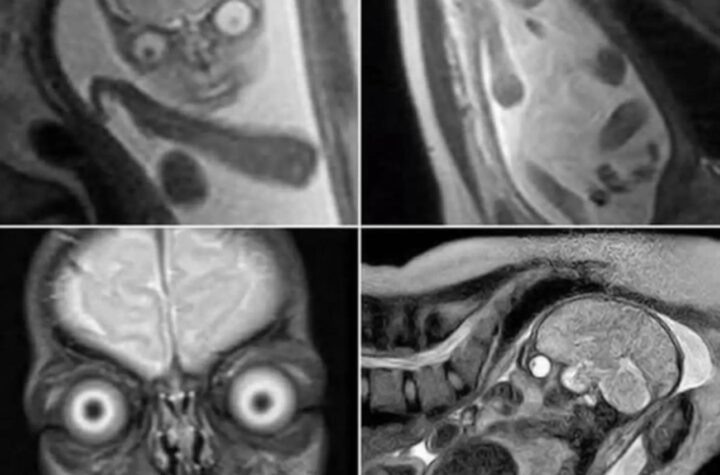

2 min read ¿Por qué se prefiere el ultrasonido sobre la resonancia magnética durante el embarazo?. – SomosACRnet 25 junio, 2025 Accidentes de Costa Rica Ambos métodos son útiles, pero uno de ellos es más seguro, accesible y adecuado para...